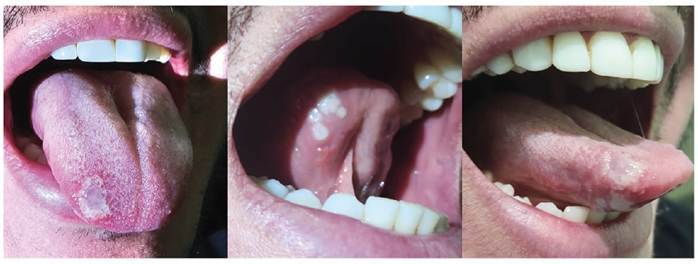

Tongue Lesions in Monkeypox.

猴痘引起的舌损。